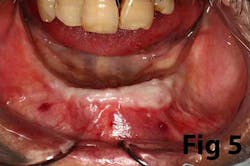

Gingival recession is the result of loss of alveolar bone and tissue, specifically AG. A high number of recession cases result in less than the minimum required amount of AG. (Fig. 4) Similarly, following tooth extraction or long-standing edentulism (without bone preservation), loss of alveolar dimension is accompanied with diminishing AG. (Fig. 5)Note: specific cases may also be attributed to gingival biotype and genetic predisposition.